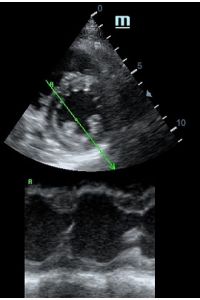

Оценка сокращения сегментов левого желудочка на глаз постепенно уходит в прошлое. Если в приборе нет функции радиального или лонгитудинального стрейна, на помощь опять может прийти Free Xros. Утолщение более 5 мм в систолу – нормальное сокращение, 2-5 мм гипокинез, истончение в систолу – дискинез.